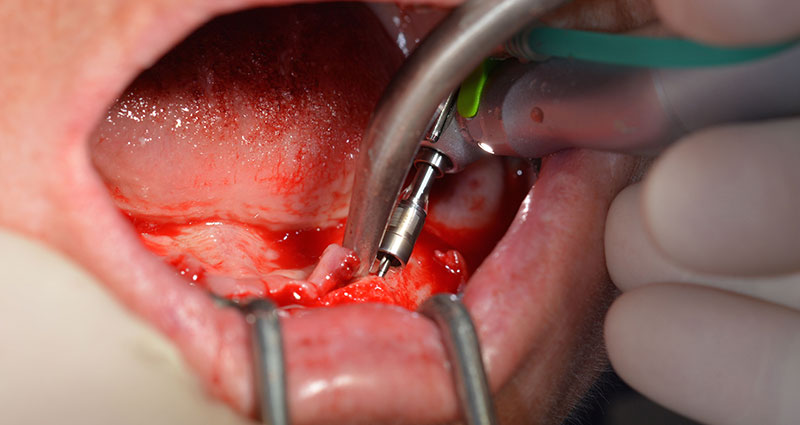

Tras la extracción de la dentición residual en el maxilar inferior, se realizó la incisión crestal en la región comprendida entre la pieza dental 37 y la 47.

A continuación, se identificó el agujero mentoniano (foramen mentale) como la estructura anatómica límite y se alisó el cortical de la cresta ósea con la pieza de mano recta y una fresa redonda grande (fig. 4).